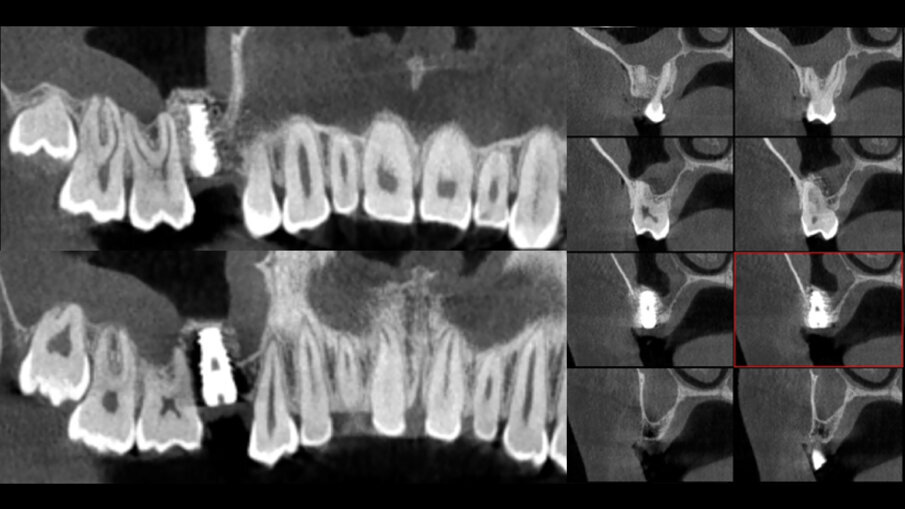

21letá pacientka se dostavila na konzultaci do stomatologické ordinace ve zdravotnickém středisku Clitrofa v Trofě v Portugalsku kvůli zavedení implantátu v anatomické oblasti zubu. V anamnéze nebyly uvedeny žádné alergie ani užívání léků. Při extraorálním klinickém vyšetření nebyly zjištěny žádné abnormality. Při intraorálním fyzickém vyšetření byla v oblasti zubu 15 patrná mírná resorpce kosti v důsledku ageneze zubu. Na skenu z CT byla v oblasti zubu 15 zjištěna výška dna sinu 4 mm, díky čemuž byl případ vhodný pro jednofázovou techniku zavedení implantátu – sendvičovou techniku (obr. 1). Na laterální stěně maxilárního sinu byly provedeny dvě vertikální osteotomie s cílem vymezit oblast kosti určenou k transplantaci štěpu. Třetí spodní horizontální osteotomie byla provedena podle dostupnosti kosti zjištěné na skenu z CT a čtvrtá horní horizontální osteotomie byla provedena za účelem vymezení výšky štěpu 10 mm. Vytvořené kostní okénko bylo vykloněno do maxilárního sinu a Schneiderova membrána zůstala neporušená. Použití fibrinu bohatého na krevní destičky při transplantaci štěpu nabízí výhody v podobě modelování zánětlivé reakce, imunitní reakce a následné opravy tkáně, reorganizace tkáně a angiogeneze. Spojení s minerálními biomateriály usnadňuje manipulaci a použití a umožňuje okamžité přilnutí k lůžku oblasti transplantace (obr. 2).

Sticky Bone byla za lehkého přitlačení umístěna do distální (palatinální) části kostního okénka. Poté byl zaveden implantát (Epikut HE, 4,5 × 10,0 mm; S.I.N. Implant System), přičemž jako primární zdroj stability posloužila stávající krčková kost. Další Sticky Bone byla umístěna do frontální části (vestibulárně) (obr. 3). Autologní fibrinové membrány vytvářejí chráněné prostředí pro regeneraci kosti v místě defektu a napomáhají osteogenezi tím, že tvoří bariéru pro infiltraci (migraci) měkkých tkání a podporují tak růst osteogenních buněk v kostním defektu.